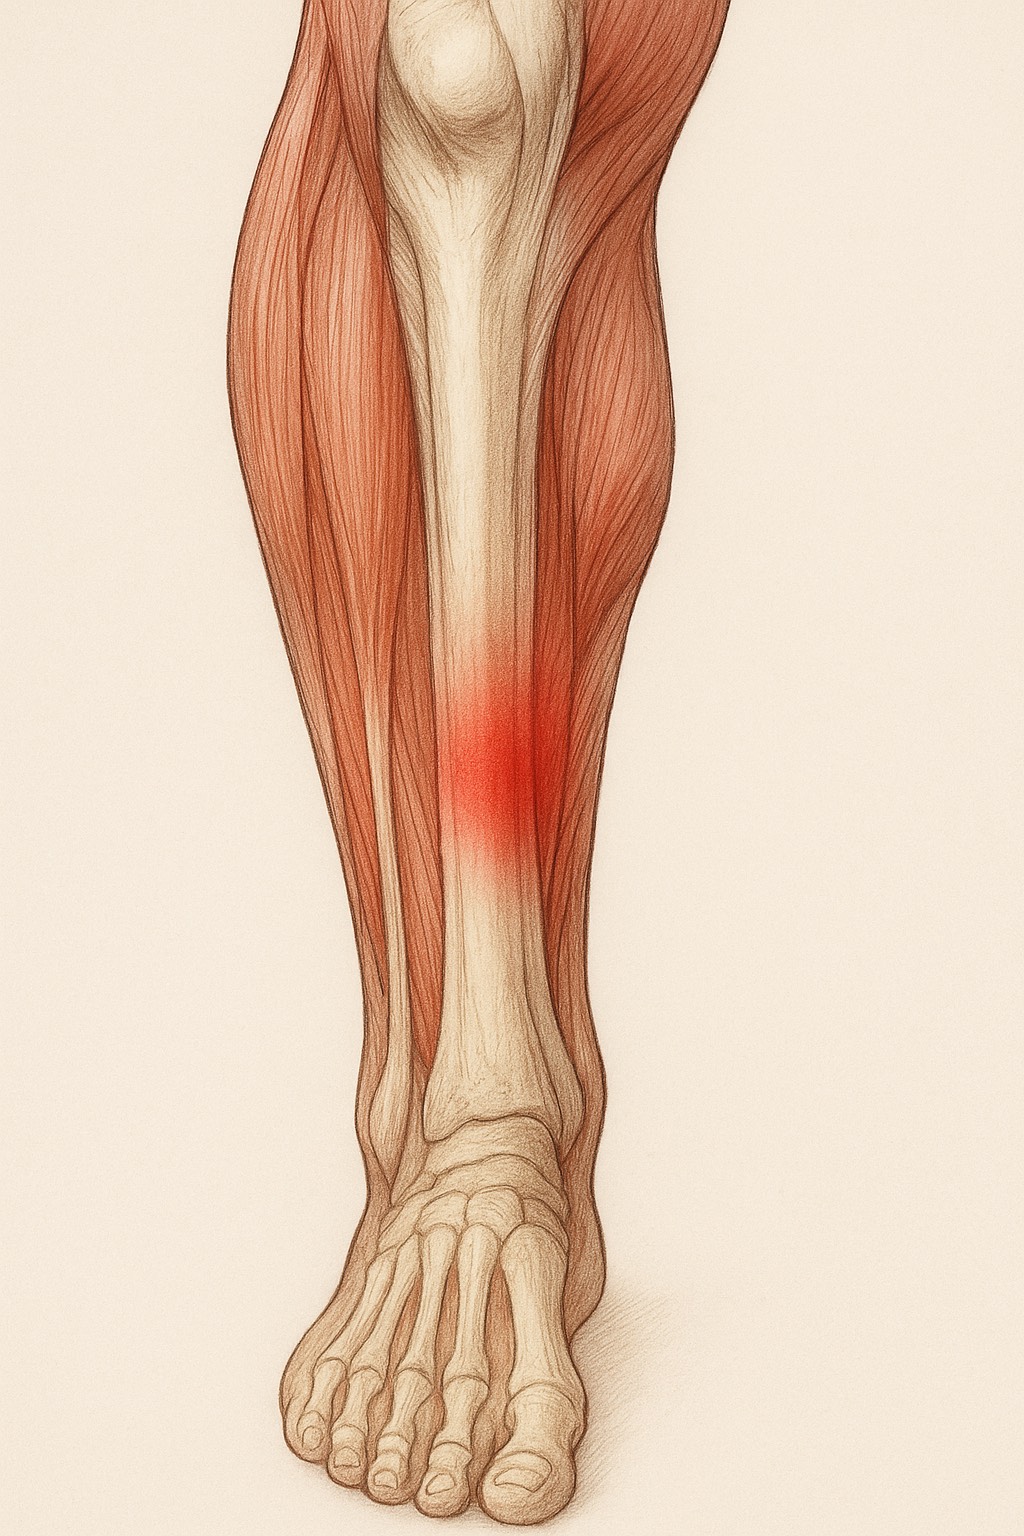

・投球動作で酷使される前腕屈筋群・伸筋群の過緊張を緩和